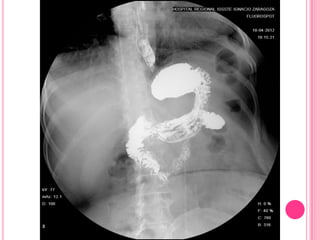

Anillo de Shatzky. SEGD que muestra una indentación de las

paredes anterior y posterior del esófago distal en relación con

anillo de Shatzky, en un paciente con hernia hiatal